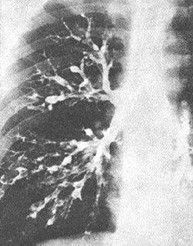

5.支氣管性肺紋理增多

表現為肺紋理粗細不勻,其中常夾雜變形紋理和小蜂窩影,常見於慢性支氣管炎、支氣管擴張等。